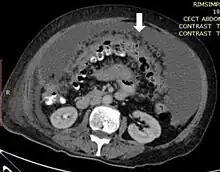

Axial abdominal computed tomography featuring omental caking due to peritoneal carcinomatosis

Due to the variety of symptoms experienced by patients with omental caking,[5] omental cakes are most frequently discovered on abdominal computed tomography (CT) or ultrasound. Plain film radiography (X-ray) is not a suggested modality for investigating the spread of cancerous cells in the abdomen due to the poor spatial resolution amongst soft-tissue densities. Contrast resolution obtained through CT allows radiologists to investigate omental caking for morphology, intraperitoneal fluid, and regional lymphadenopathy assists in proper diagnosis so clinicians, surgeons, and oncologists can plan the appropriate course of treatment.[8]